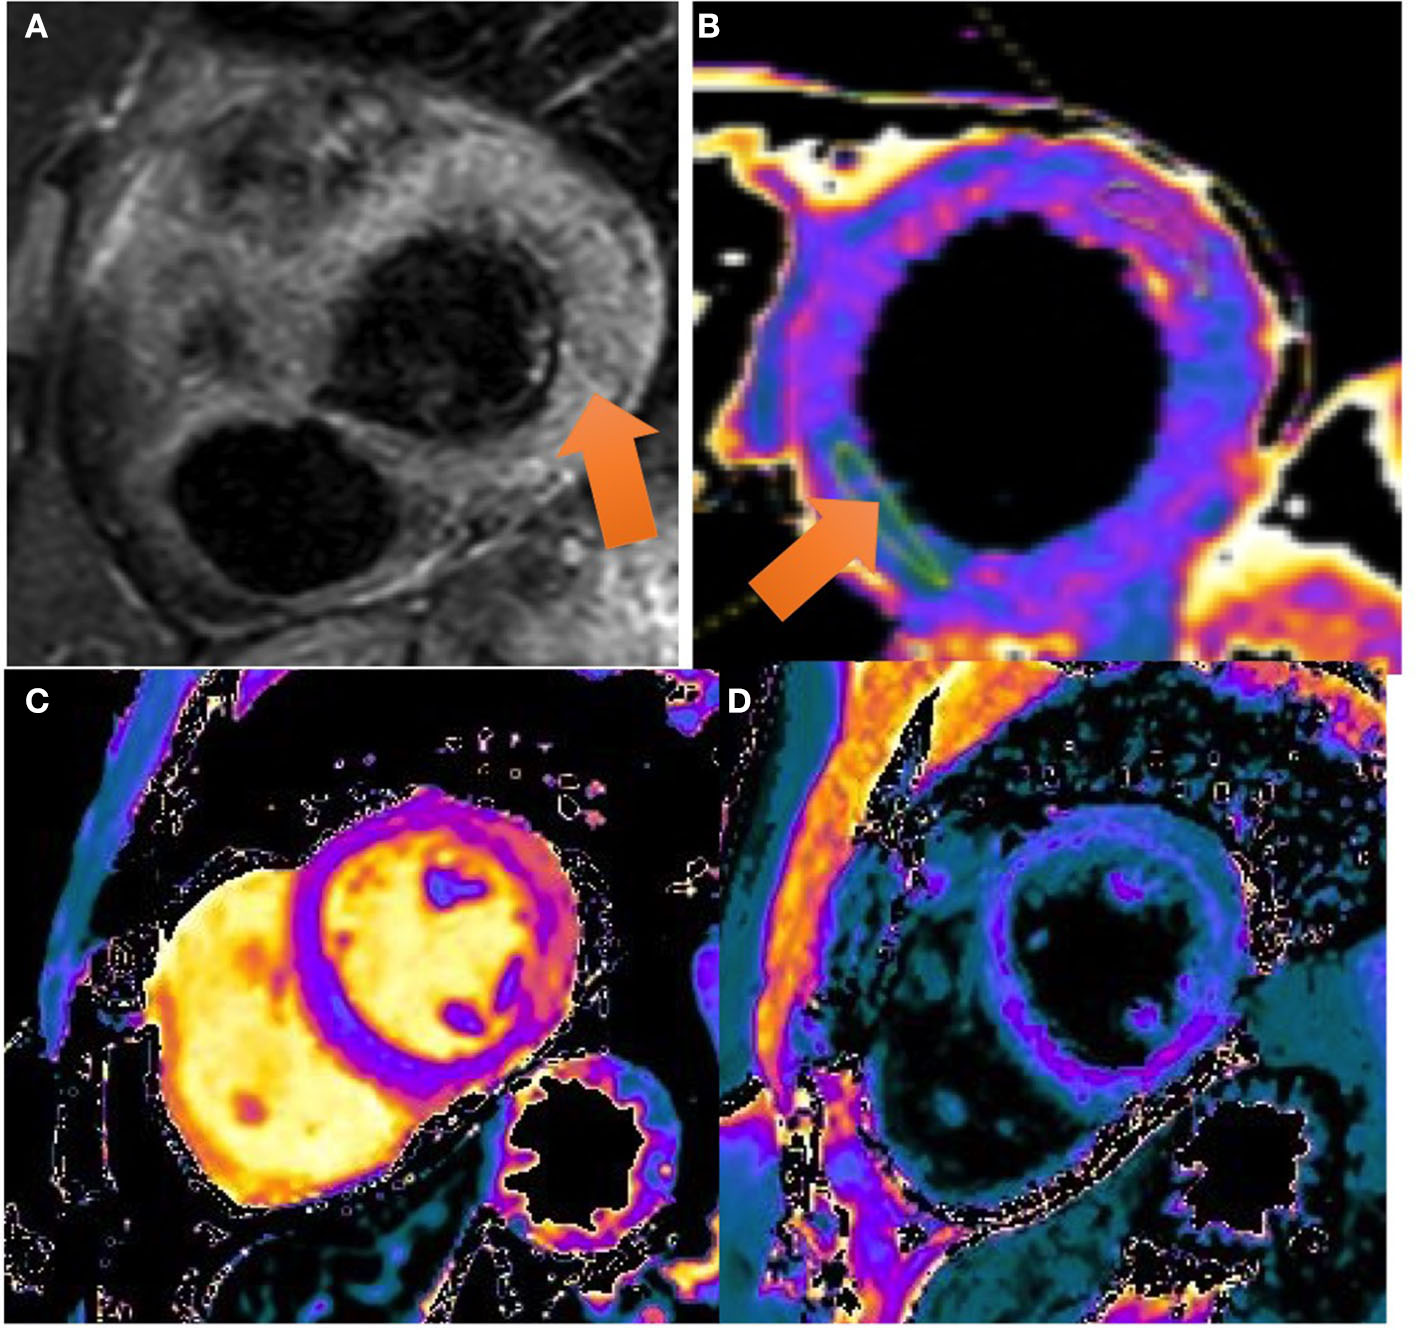

Figure 2

CMR images: the balanced FFE (fast field echo) sequences acquired along the short axis (A, B) and two chamber (C) and four chamber (D) views demonstrate myocardial late gadolinium enhancement with epicardial predominance in the lateral and inferior wall and mesocardial predominance in the septum and anterior wall (view arrows).

Figure 3

CMR images: (A) T2 STIR sequence: a high ratio (> 2) is seen in the intensity between the myocardium and the skeletal muscle compatible with a generalized edema. Color-coded image of T2 mapping in LV mid-chamber. The arrow marks an increased T2 value (T2 = 60 ms) in the lateral and inferolateral wall. (B) Color-coded image of T2 mapping in LV mid-chamber. The arrow marks an increased T2 value (T2 = 60 ms) in the lateral and inferolateral wall. (C, D) T1 mapping and T1 enhanced mapping, respectively. In T1 mapping, extensive area of increased T1 value (view pink and orange areas) in lateral and inferolateral walls. On quantitative analysis, values on the native T1 map were 1,160 ms (normal value 1,025–1,075 ms). In T1 enhanced mapping, these areas area correlated with increased extracellular volume (ECV).

Cardiac Magnetic Resonance (CMR) performed on day 6 showed a preserved left ejection fraction (56%) with no regional wall abnormalities. An increased myocardial and pericardial signal intensity on the T2 STIR sequence was suggestive of edema (Figure 2A). On the T1 mapping, an average native T1 of 1,160 ms was observed, and on the T2 mapping, an average T2 of 60 ms was observed. In addition, the quantitative assessment of the cardiac ECV (extracellular volume) was 35%. The T1 and T2 mapping values were measured on a 1.5 Tesla MR Philips machine within a single breath-hold using a modified Look-Locker with inversion recovery (MOLLI) and gradient and spin echo (Gra-SE) sequences, respectively. Normal native myocardial T1 values lie between 1,025 and 1,075 ms, whereas T2 values lie between 50 and 57 ms (internally validated). A color-coded image of T2 mapping (Figure 2B), native T1 (Figure 2C), and enhanced T1 mapping (Figure 2D) were also performed. Late gadolinium enhancement (LGE) images, obtained by using a balanced fast field echo (FFE) sequence, showed subepicardial and mesocardial enhancement of the myocardium and mild signs of pericarditis, which were considered consistent with acute myopericarditis (Figures 3A–D). The patient met all modified Lake Louise criteria for myocarditis: T2 criteria (myocardial edema shown on a T2 STIR sequence and T2 mapping) and T1 criteria (non-ischemic myocardial injury shown on an LGE sequence and T1 mapping). Signs of mild pericarditis were also exhibited.